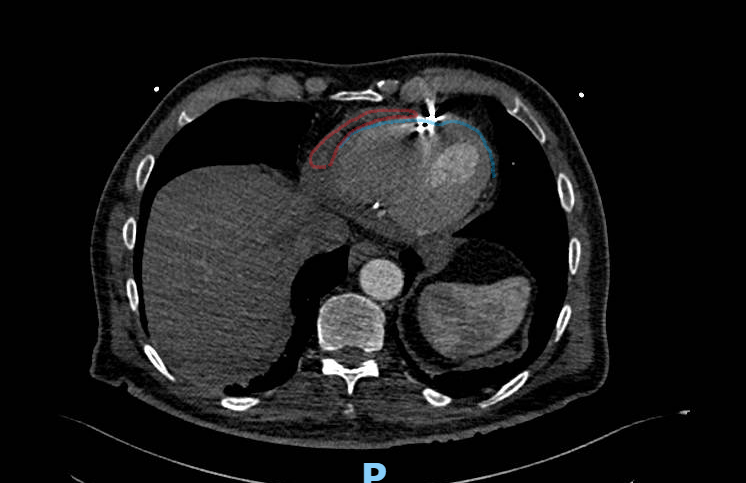

Diagnosis and management of iatrogenic cardiac perforation caused by pacemaker and defibrillator leads

Best method CT , some difficult with star artifact from the cable

Diagnosis and management of iatrogenic cardiac perforation caused by pacemaker and defibrillator leads

Best method CT , some difficult with star artifact from the cable